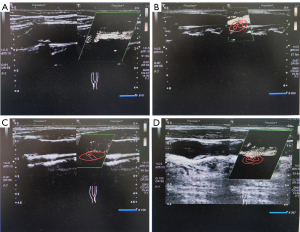

In this study, unstable plaques were defined according to the imaging characteristics observed on high-resolution ultrasound, including (I) an irregular or ulcerated plaque surface; (II) the presence of intraplaque hemorrhage; and (III) a high degree of IPN (grade 2 or 3). ICEs, such as TIA or acute ischemic stroke, were recorded as clinical outcomes and not used to define plaque instability. For the examination, a color Doppler ultrasound diagnostic device (HERA W10, Samsung, Korea) with a probe frequency of 9–14 MHz was used, with the patient positioned supine with the head turned to the contralateral side to fully expose the carotid artery. Initially, the conventional mode was employed to identify the target plaque location. After the largest plaque was determined, the examination parameters are adjusted to the SMI mode. The carotid artery, artery bifurcation, and carotid bulb were then scanned in transverse and longitudinal sections. The thickest part of the target plaque in the longitudinal section was selected, and the gray-scale mode was engaged for scanning. The scanning depth was set to 3 cm, with a duration of 60 seconds, for observation of the blood flow signals within the target plaque. SMI blood flow grading was classified into four levels (5): grade 0, no blood flow signal within the plaque; grade 1, one or several punctate blood flow enhancement signals within the plaque; grade 2, punctate or 1–3 linear blood flow enhancement signals within the plaque; and grade 3, multiple linear enhancement signals within the plaque, some traversing the entire plaque (Figure 1). In this experimental study, the measurements and recordings during the SMI examination were performed by a single physician with over 3 years of experience in vascular ultrasound examinations according to standardized operating procedures.